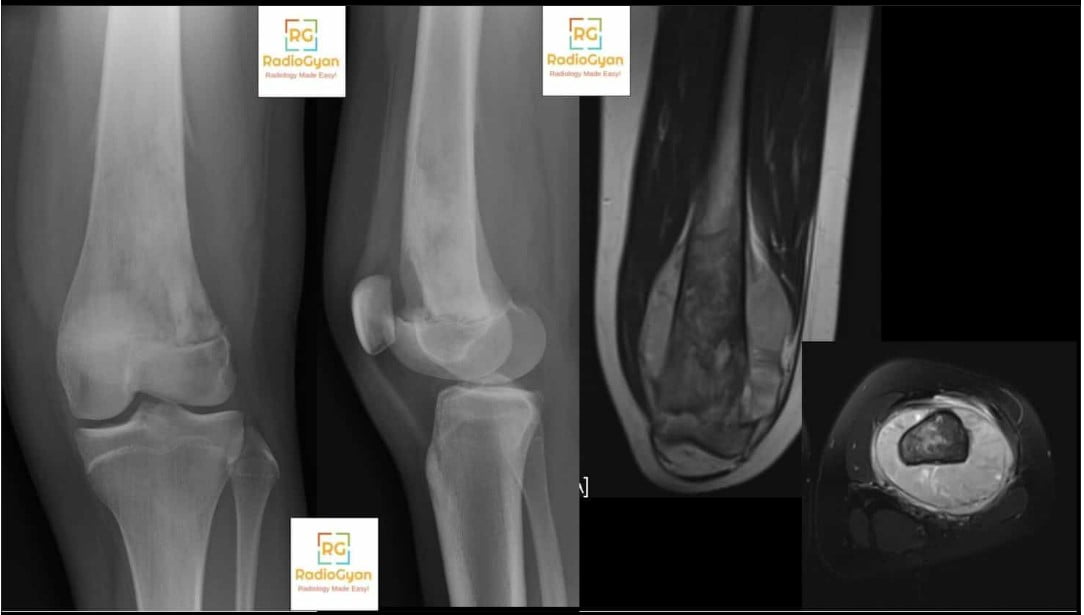

Codman triangle is caused by a rapidly growing lesionโmost often a tumor such as osteosarcoma or Ewing sarcoma, but also possibly infection, hemorrhage, or abscessโthat elevates the periosteum away from the underlying cortex faster than the periosteum can respond with new bone formation. This results in a characteristic radiologic appearance where the periosteum, partially ossified at its margins, forms a triangular or โVโ-shaped reaction visible at the margin of the lesion on imaging modalities. The sign is strongly associated with aggressive bone lesions, including primary bone malignancies (osteosarcoma, Ewing sarcoma, chondrosarcoma), metastatic disease, aggressive benign tumors (aneurysmal bone cyst, giant cell tumor), and osteomyelitis.

A Codman triangle forms because an aggressive lesion grows so rapidly that it outstrips the ability of the periosteum to lay down new bone in organized layers. Instead of producing a smooth, continuous periosteal reaction (such as seen in benign, slow-growing processes), the lesion abruptly lifts the periosteum, which then forms a thin shell of new bone at its edges. The central portion of the elevated periosteum does not ossify, creating a two-sided, V-shaped or triangular area of new bone at the junction of the elevated periosteum and the cortexโoften with a third side left open, hence the โtriangle.โ